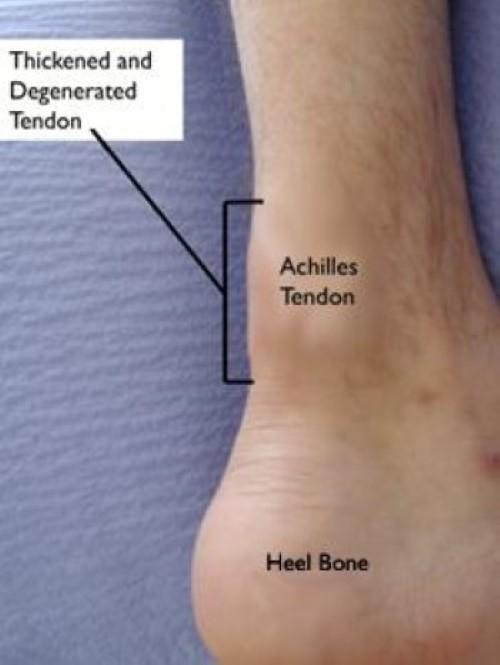

You may also come across the term "tendinopathy," which is used to describe a condition in which the tendon develops microscopic degeneration as a result of chronic damage over time. Tendinitis, tendinosis, and tendinopathy are all common terms which essentially refer to the same problem.

In noninsertional Achilles tendinitis, fibers in the middle portion of the tendon (above where it attaches to the heel) are affected. Over time, the fibers may begin to break down and develop tiny tears. This can lead to tendon swelling and thickening.

Insertional Achilles tendinitis involves the lower portion of the tendon, where it attaches (inserts) to the heel bone (also known as the calcaneus).

In both noninsertional and insertional Achilles tendinitis, damaged tendon fibers may calcify (harden) over time. Bone spurs often form on the heel with insertional Achilles tendinitis.